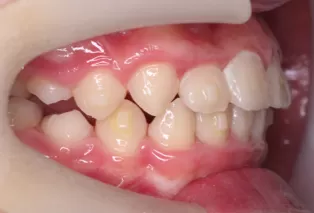

Intraoral photos